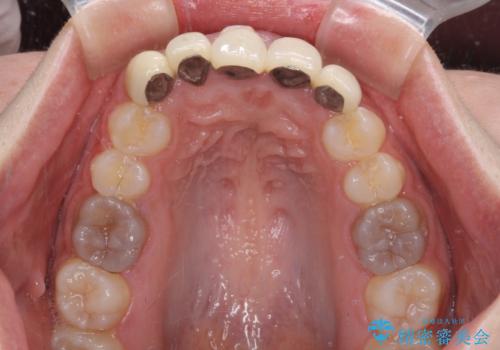

- 歯列不正を改善する目的で装着した前歯のセラミックが気になるとのことで来院された患者様です。

金属の裏打ちを用いたセラミッククラウンであったため歯肉縁に黒ずみが見えてくることは良くありますが、全体的に歯列が不揃いであることが気になったので、それらをオールセラミッククラウンにて改善することとしました。

セラミッククラウンが外れてしまうことを心配して、歯ブラシをあまり当てられなかったとのことで、歯肉に軽度の炎症が認められました。